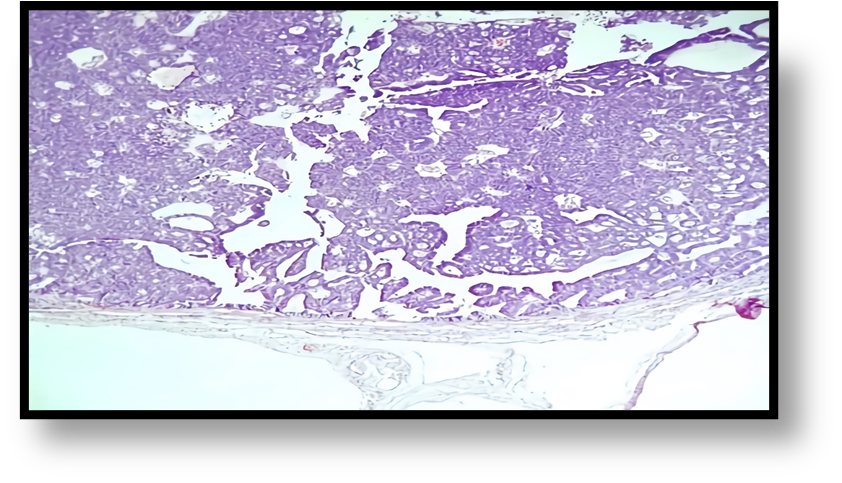

Diagnosed with a benign right adnexal tumor, a laparotomy was performed that revealed a 15x12 cm right ovarian tumor with a cystic component and a 14x5 cm right hydro salpinx with chocolate-like content through its wall (Figure 3). Total hysterectomy plus bilateral salpingo-oophorectomy was performed with a report of ovarian cystadenoma and endometroid adenocarcinoma of the right Fallopian tube. It showed dilation and the section revealed a nodular lesion, in its distal third, with a papillomatous appearance, white-yellowish, of a soft, sessile consistency, with endophytic growth of 2x1.5x.2cm (Figures 4, 5). The microscopic study showed a neoplasm of epithelial origin with a glandular, cribriform, papillary and even solid growth pattern that did not infiltrate the underlying capsule, (Figures 6, 7, 8).

Figure 8: 10x microphotography. Endometrioid adenocarcinoma showing capsule of origin and solid and cribriform pattern.

The microscopic description of this neoplasm is characterized by showing an architecture that varies between glandular, papillary and solid formation with cells showing endometrioid differentiation [7, 10, 13]. In our case, the microscopic study showed a nodular endometrioid carcinoma with papillary formations, a solid, cribriform pattern and with few mitoses, characteristics that correspond to endometrial endometrioid carcinoma [2.8].